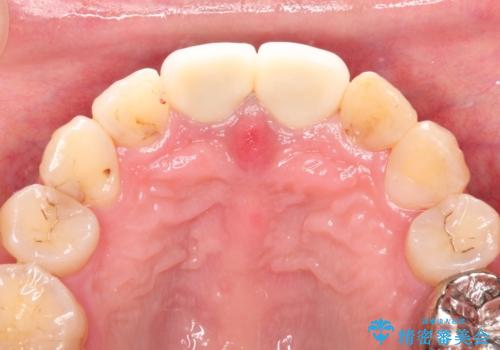

変色した前歯をセラミックできれいに レイヤリングセラミック

- 仮歯の製作→ワックスモデルの試適合による形態の確認→セラミックの完成

前歯のセラミック治療では、他の歯と色調をそろえるのが非常に難しいです。

他の歯に亀裂や白濁など複雑な色合いがある場合、それらをセラミックで再現することも可能ですが、スタンダードのオールセラミックではある程度の同調となります。

かぶせ物の種類: PFZ standard